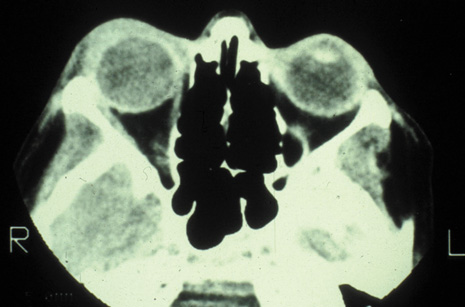

Magnetic resonance imaging (MRI) is purported to be more useful than CT in the diagnosis of preseptal cellulitis. It is less reliable at diagnosing the subtle signs of muscle enlargement and periscleritis and thus is not as useful in differentiating orbital cellulitis from other inflammatory orbital diseases.71 On MRI with gadolinium contrast, orbital cellulitis may show a smearing or linear streaking of the normal fat shadows on T2-weighted images. MRI is excellent for demonstrating localized fluid collections such as abscesses. It is not helpful in distinguishing a transudate from an exudate, because both appear liquid and are of low intensity on T1-weighted images and bright on T2-weighted images (Fig. 19).

Fig. 19. Magnetic resonance image of preseptal cellulitis with anterior abscess formation.

MRI is superior to CT in the diagnosis of cavernous sinus thrombosis. T2- and proton-weighted images show high signal luminal narrowing as well as absent flow or localized parenchymal infarcts (Fig. 20).72 Absent flow can be demonstrated as well in the superior ophthalmic vein in cases of carotid or cavernous sinus thrombosis.72 MRI with gadolinium can help define these abnormalities and can detect dural invasion.

Fig. 20. Cavernous sinus thrombosis. Axial T1 image shows cavernous carotid luminal narrowing on right and enlargement of right cavernous sinus. Note extensive sinus disease.